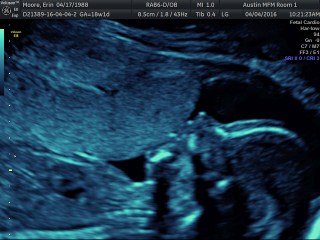

Today we had a super long appointment with Dr. Horton. We had a full anatomy scan of Jackson and ended up not having to do any blood-work, so that was a bonus! While he did not cooperate well for a good 3D face picture, he was in a great position for the echo part of the ultrasound. We got to watch his heart beating for a long time. Even Jordan and I could clearly see all 4 chambers of his heart pumping away. He is about 10″ long, 9 ounces, and has a perfectly beating heart. It was just amazing to watch. We saw 10 fingers and 10 toes, arms and legs, bladder and kidneys, and everything else. We just stared at the screen in excitement and amazement.